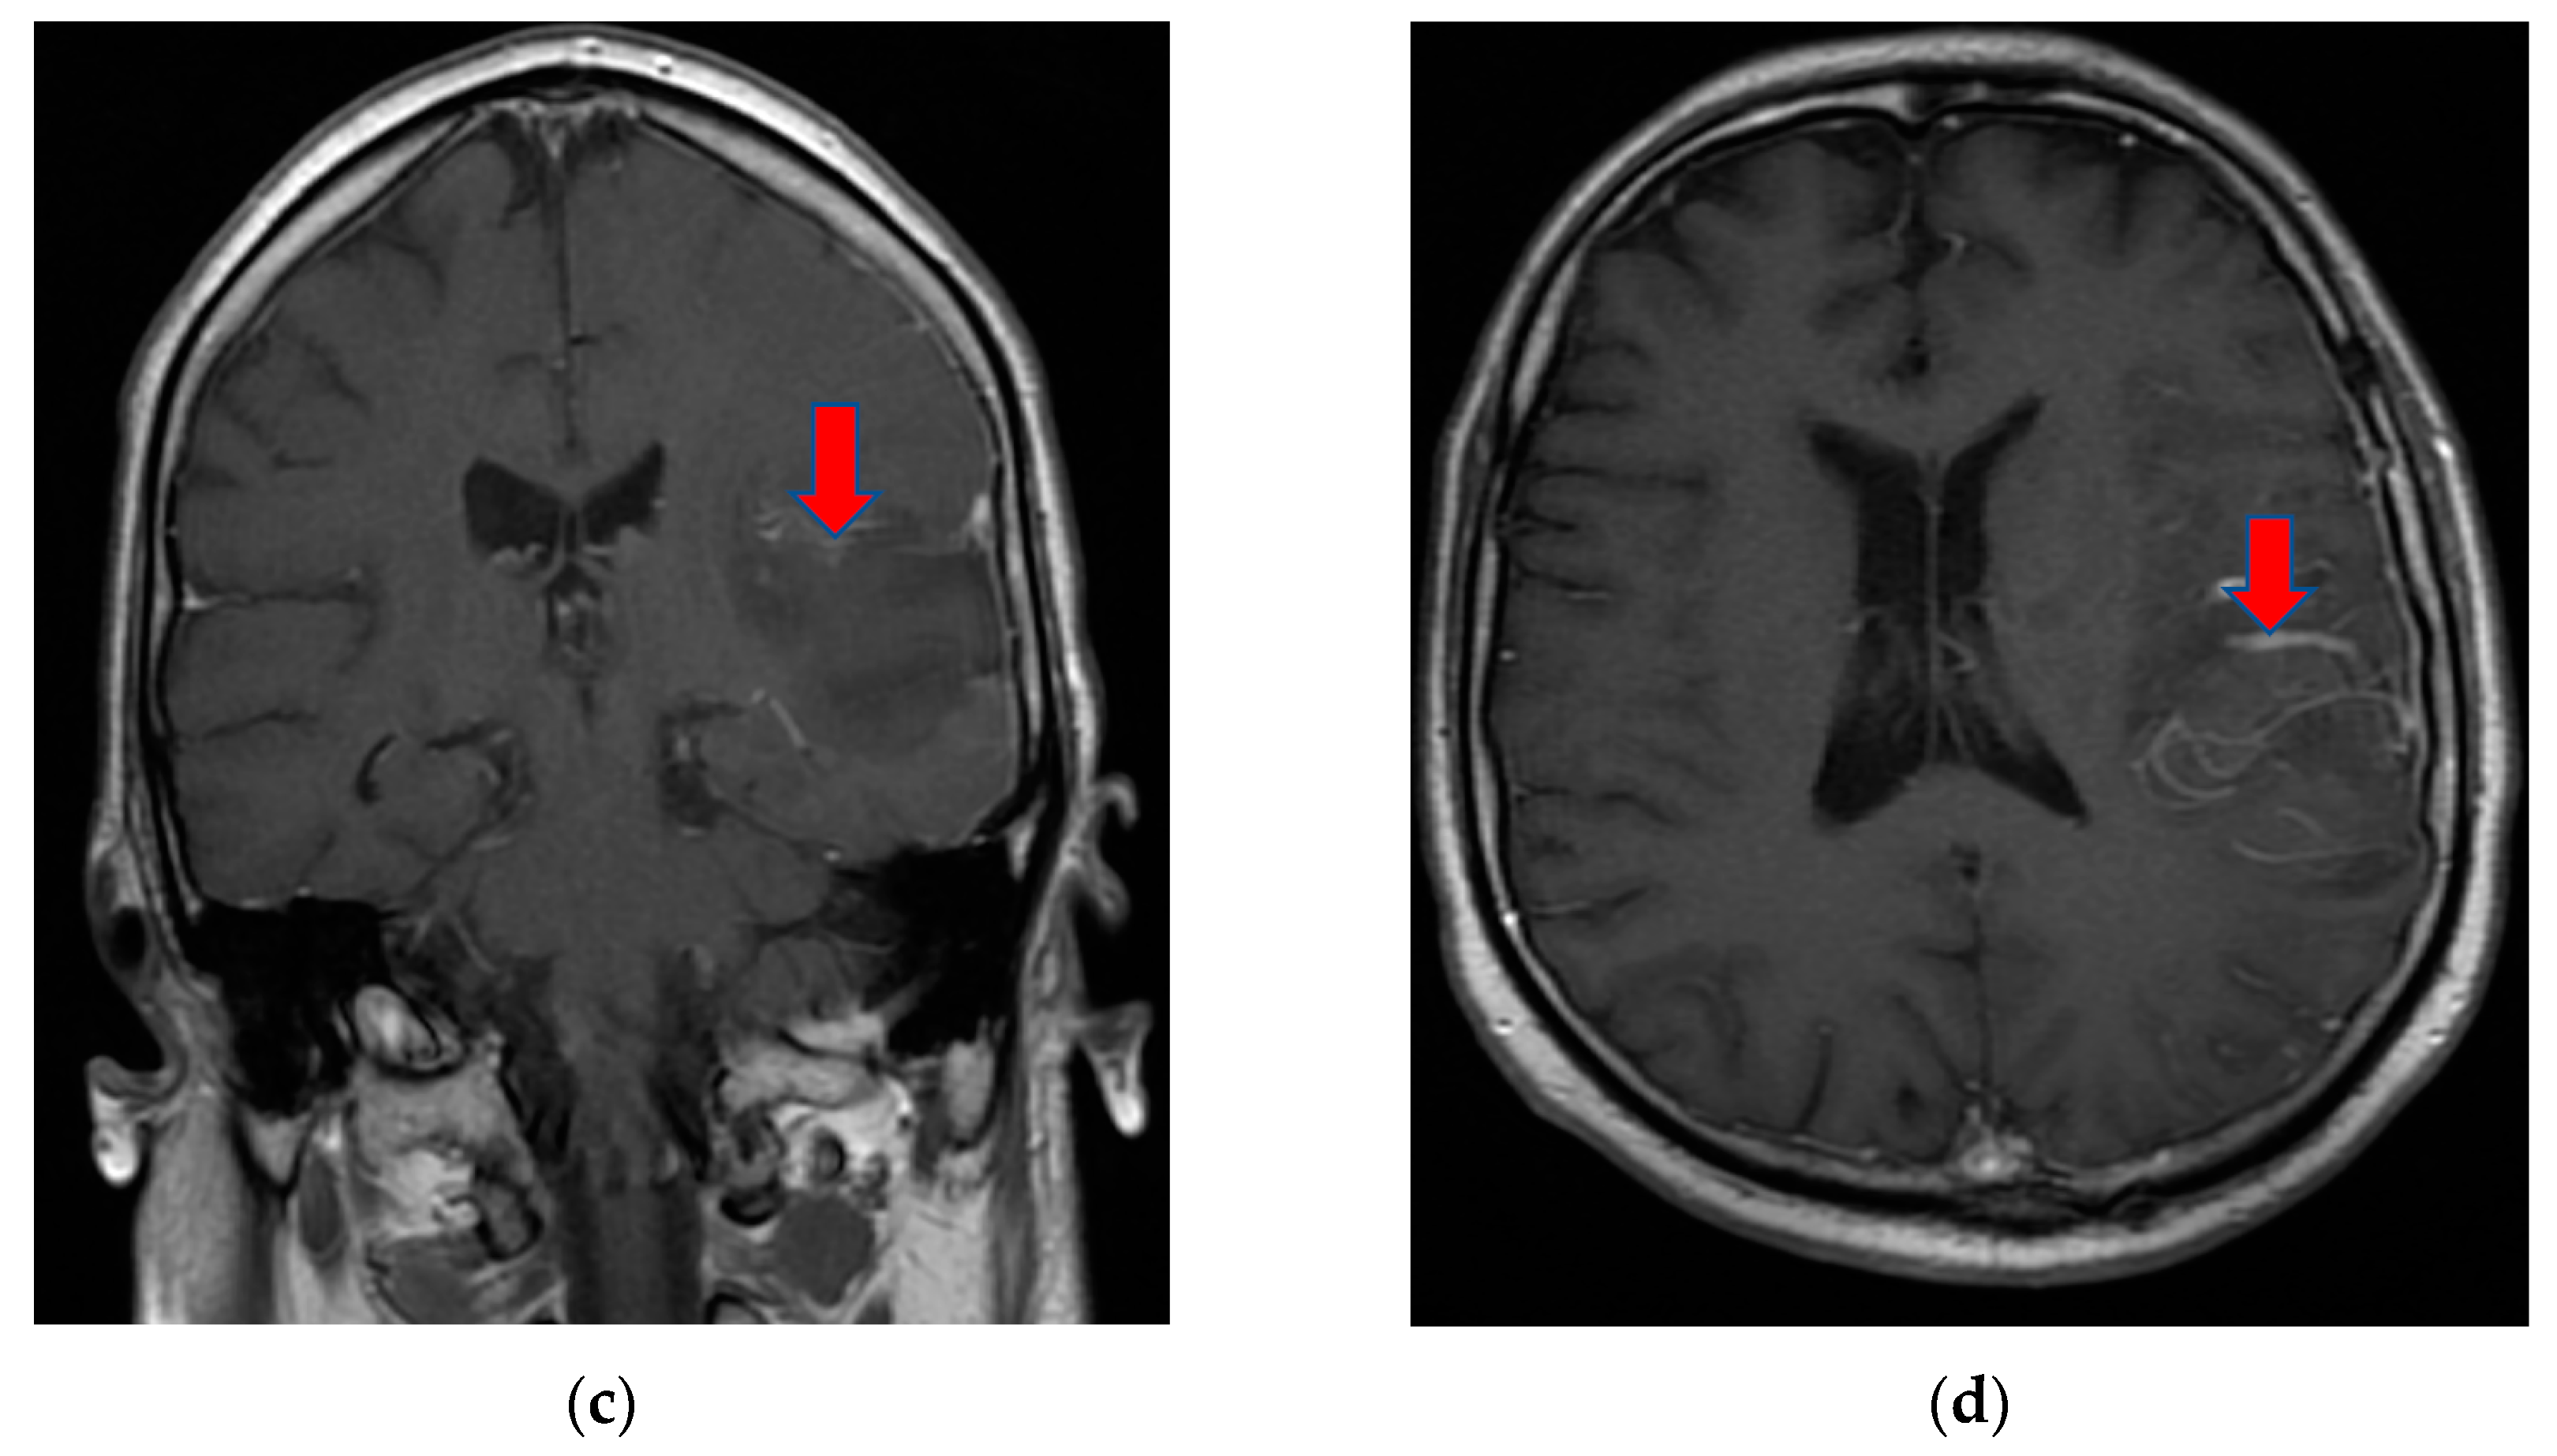

Contrast-enhanced head-computed tomography (head-CT) was conducted upon hospital admission and demonstrated hyperattenuation of the left cavernous sinus and left lateral sinus, which was concerning for sinus thrombosis. MRI of the brain and orbits with and without contrast, in addition to magnetic resonance angiography (MRA)/magnetic resonance venography (MRV) of the head, showed an inflammatory process in the areas of the left cavernous sinus and orbital apex with perineural enhancement surrounding the left optic nerve sheaths. The presence of thrombus in the cavernous sinus was refuted by cerebral MRA/MRV. No vascular malformation of the left internal carotid artery was found. The MRI findings were suggestive of Tolosa–Hunt syndrome (Figure 1).

Figure 1. MRI T2 axial Flair (a) and coronal T1 FSE (b) images demonstrated perineural tissue extending into the left cavernous sinus. Postcontrast T1 axial FSE (c) and coronal T1 FSE (d) images showed an inflammatory process involving the left cavernous sinus and orbital apex with perineural enhancement surrounding the left optic nerve sheath. MRI: magnetic resonance imaging; Flair: fluid attenuated inversion recovery; FSE: fast spin-echo.